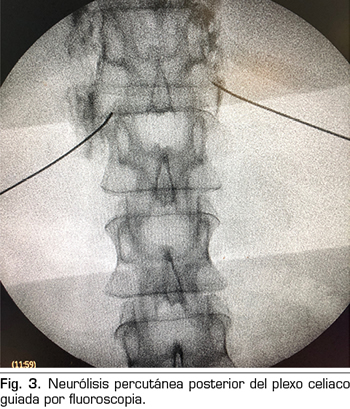

Figura 3